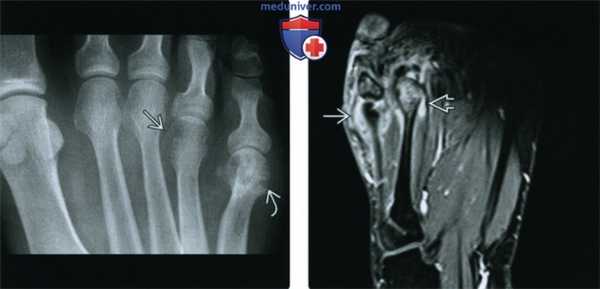

(Слева) Рентгенография в ЗП проекции: типичное для РА сужение хряща, преимущественно в ПФС га и небольшие краевые эрозии ПФС. Тем не менее, эти признаки не столь показательны, как крупные субхондральные кисты, которые визуализируются в нескольких местах. Обратите, также, внимание на нормальную плотность костной ткани. Этот мужчина 52 лет имеет стойкий РА.

(Справа) Рентгенография в ЗП проекции: отек мягких тканей противоположной кисти (предположительно синовит) га и крупные, симметрично расположенные субхондральные кисты, подтверждающие диагноз. (Слева) Рентгенография в ПЗ проекции: сужение хряща в 1-м плюснефаланговом суставе и множественные, имеющие типичное для РА расположение, мелкие краевые эрозии. Тем не менее, на стопе определяется нормальная плотность костной ткани и чрезмерно крупная субхондральная киста, что искажает типичную картину обычного РА. Совокупность признаков у этого мужчины, не предъявляющего значительных жалоб на болевой синдром, соответствует устойчивому РА.

(Справа) На другой столе визуализируются эрозии и нормальная плотность костной ткани, однако меньше кист. Высокий уровень ревматоидного фактора подтверждает диагноз.